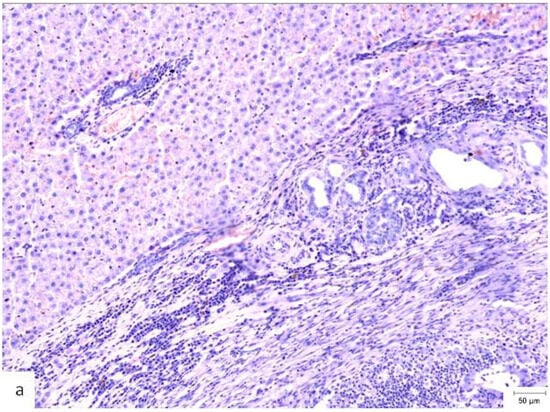

Figure 2.

Granulomatous foreign-body reaction observed in the perihepatic tissue from a rat in the Study group (CA + PLA) at PO day 150 (Hematoxylin and Eosin stain, ×40 magnification). A dense infiltrate composed predominantly of histiocytes and scattered lymphocytes surrounds the residual biomaterial. Multinucleated foreign body-type giant cells are evident within the fibrotic stroma, indicating a sustained chronic inflammatory response to the adhesive compound. Scale bar (right lower corner): 20 µm.

High-grade fusion (scores of 2–3) was observed in 9/14 (64.3%) of the CA + PLA implants versus 1/14 (7.1%) of the TachoSil® and 0/5 of the cautery animals. When calculated as n (%), is the percentages were 64%, 7%, and 0%. The medians were 2 [1–2.8] for the Study group, 0 [0–1] for the TachoSil® group, and 1 [1–1] for the Control group. The Kruskal–Wallis test produced an H of 16.04 (p < 0.001); the CLMM gave an aOR of 9.7 (3.0–31.2, p < 0.001) for the Study vs. TachoSil® group comparison. This means that out of every 100 patients, ∼64 could develop pronounced FBGC layers with the PLA patch versus < 10 with the fibrin sealant (Table 8). Granulomatous foreign body reactions could be observed in the perihepatic tissue of the S group at PO day 150 (Figure 2).